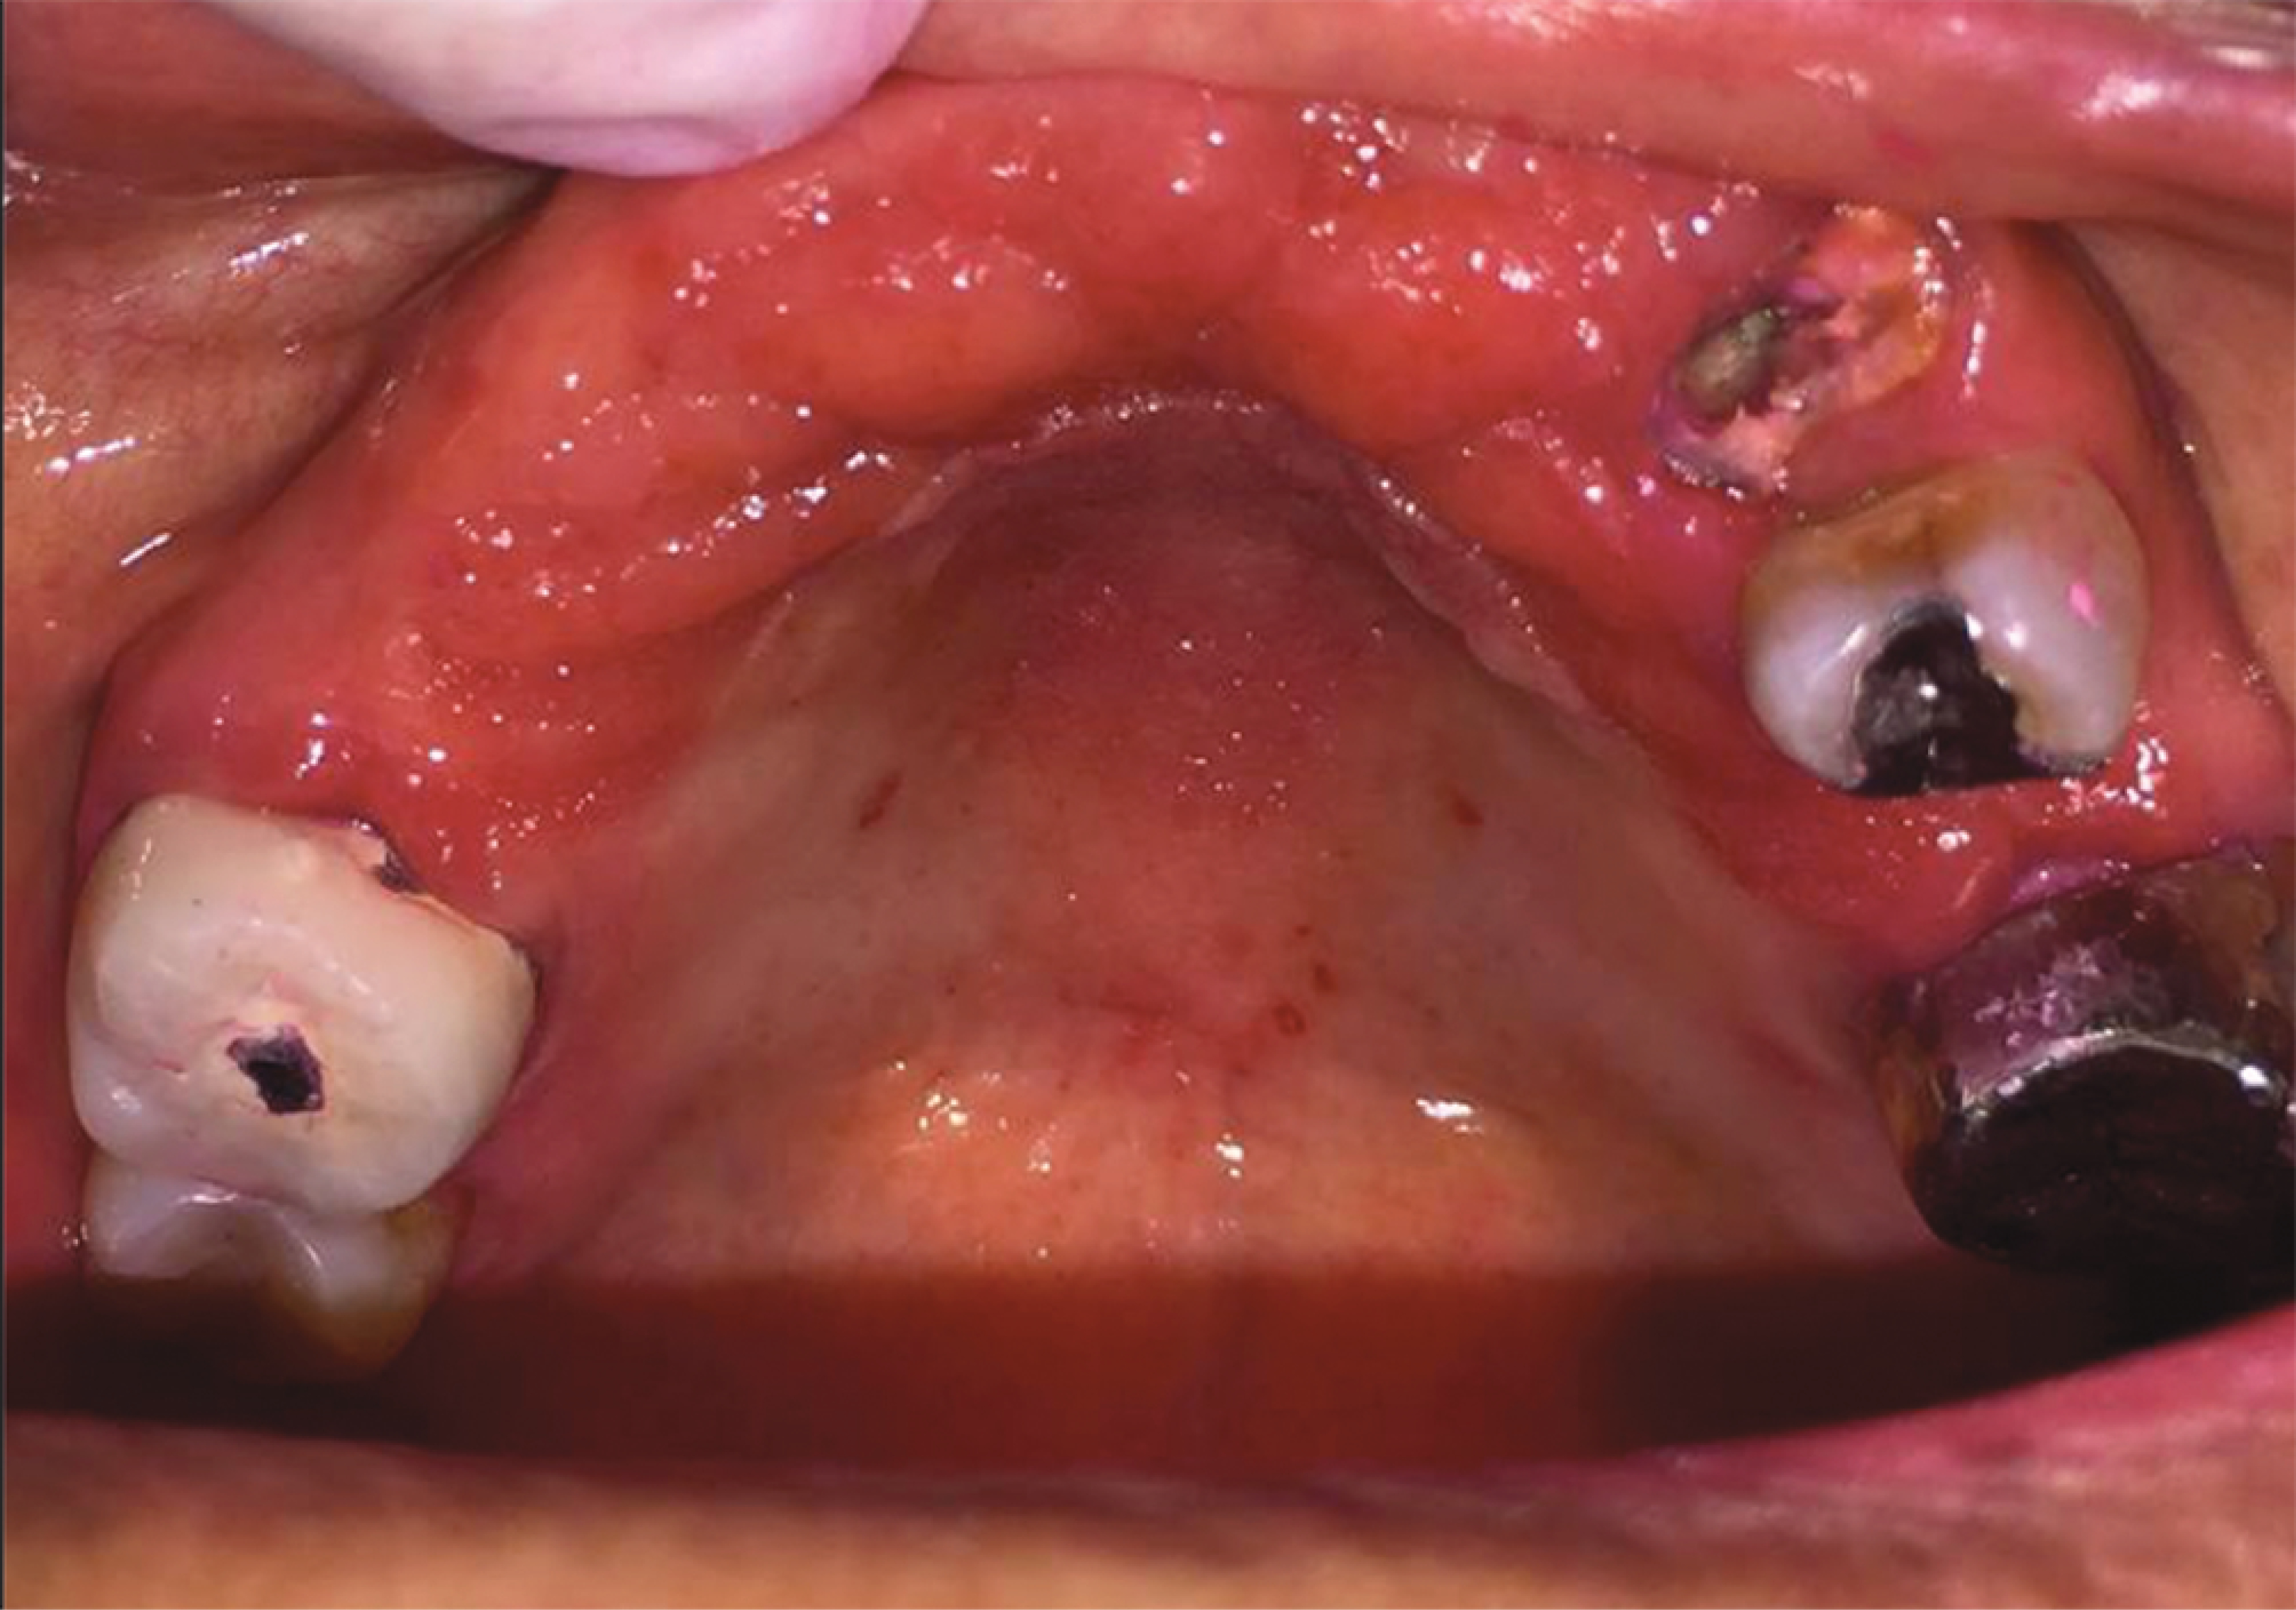

Figure 4